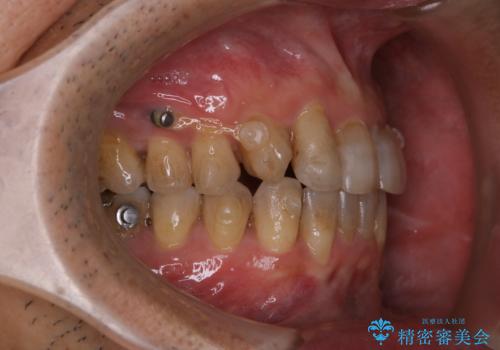

- マウスピース矯正中(インビザライン)に着色落としをしたいとのことでした。PMTC60分コースを行いました。

PMTC(保険外治療)は、毎日の歯磨きで落としきれない汚れや、コーヒ、紅茶・タバコのヤニなどの着色も除去します。目には見えない歯と歯の間・歯肉の境目・インビザライン中はアタッチメント周囲などに残っているプラーク(歯垢)もしっかり取り除きます。PMTCでは専門的な機械や材料を使用して、徹底的に汚れを除去するため、虫歯・歯周病・口臭予防などにつながります。